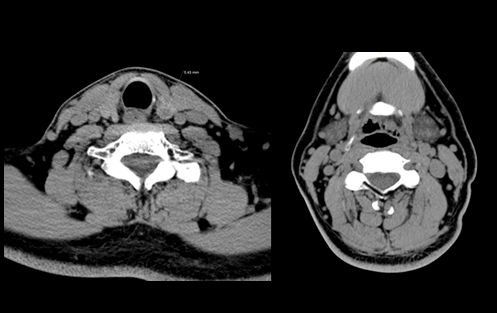

臨床圖像